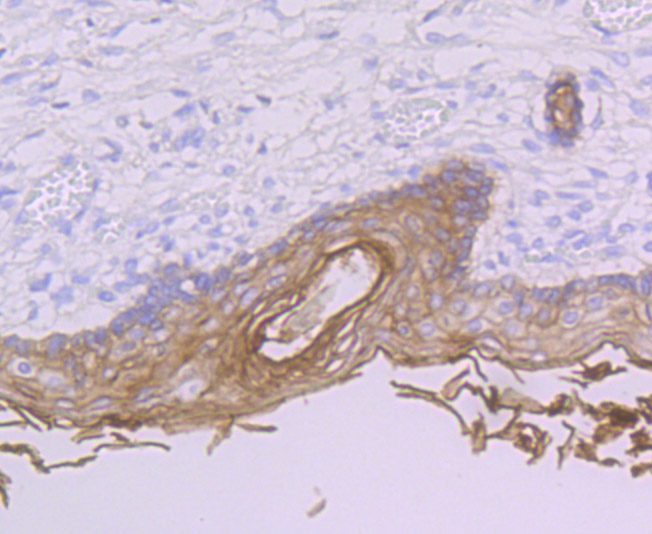

Immunohistochemical analysis of paraffin-embedded human skin tissue using anti-PERP antibody. Counter stained with hematoxylin.